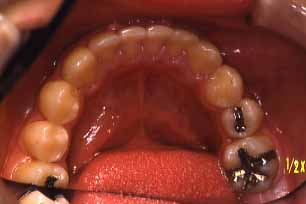

上顎

(ミラー像)

下顎